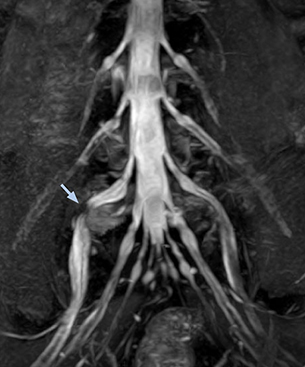

“In such case, we would then browse through axial T2-weighted MR images slice by slice and mentally reconstruct the actual situation based on both radiculography and MRI. Fortunately, NerveVIEW can now very well show nerve courses and presence of nerve compression or edema in one single image series.” “We have often seen NerveVIEW directly depict details of the nerve compression that were not observed by radiculography. Therefore, we think that with NerveVIEW we can reduce the number of invasive examinations, especially for some patients with lumbar plexus symptoms.”

The key concept in MR neurography, Dr. Yabuki stresses, is the ability to directly visualize spinal nerves, versus inferring the presence of pathology indirectly. “Before NerveVIEW, we estimated compression of the nerve by looking for the presence or absence of fat signal on other MR images,” he says.

“For example, in sagittal images, when the presence of fat is observed in the intervertebral foramen, it suggests that there is a margin around the nerve. Similarly, the absence of fat indicates that the nerve is being compressed. So, we used to deduce nerve compression indirectly. With NerveVIEW, however, we can observe the condition of the nerves directly, regardless of the presence or absence of fat. We always prefer such direct observation of anatomy over having to make an inference about it.”

“Although symptoms of typical disc herniation and atypical hernia are very similar, the actual site of herniation is different. It is therefore important to characterize the nerve’s condition both inside and outside of the intervertebral foramina. “Conversely, if we see no abnormality in NerveVIEW, we can assume at least that there is no severe condition that requires surgery. Like this, it can help us avoid unnecessary surgery. NerveVIEW can have a tremendous impact in this way.”

“NerveVIEW is really useful for those cases where a nerve disorder is strongly suspected based on the clinical examination but our regular MRI images do not show any findings. These atypical herniations and spinal canal stenosis, occurring in 5% to 15% of the total lumbar herniation/stenosis cases are our main target when using NerveVIEW,” says Dr. Yabuki.

“The intra-luminal signal of veins, especially around the intervertebral space, can be suppressed well with NerveVIEW. As a result, we can easily observe the detailed nerve structure around the posterior ganglion,” he says. “This is why we use 3D NerveVIEW for intraforaminal stenosis and extraforaminal stenosis/herniation (lateral disc herniation). On the other hand, if herniation is suspected to exist inside the dorsal root ganglion (DRG), balanced TFE or ProSet-FFE is applied. NerveVIEW is not suitable for evaluating the median type of herniation.” The SE-EPI DWI-based method for MR neurography works well for large FOV exams like whole-body MRI, but focal examination of nerves is often limited by the attainable spatial resolution (both inplane and slice direction) and geometric distortion. “3D NerveVIEW achieves higher in-plane resolution – close to our other routine spine sequences – and the source images can be used instead of adding a fat-suppressed T2-weighted sequence,” Tanji says.